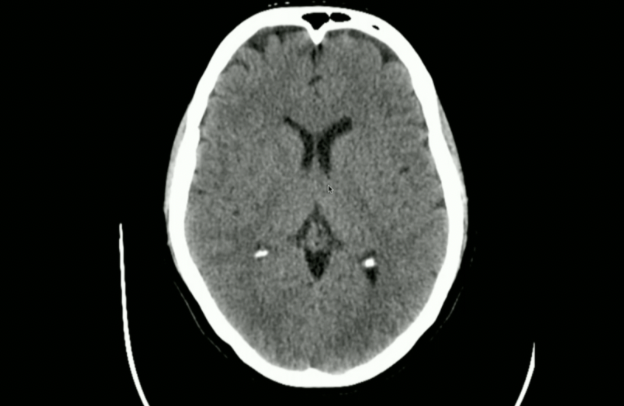

<p>Is this normal/abnormal?</p>

Is this normal/abnormal?

• Normal: the Choroid Plexus can Naturally Calcify